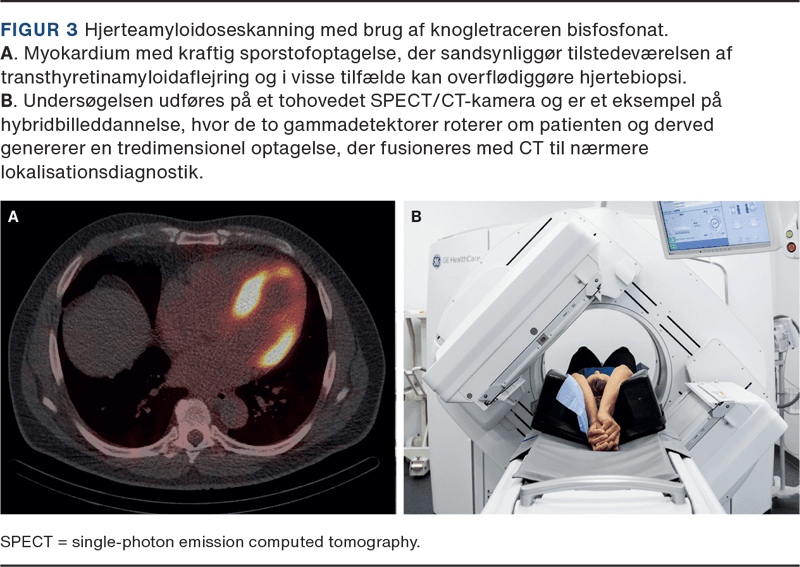

Klinisk fysiologi og nuklearmedicin har en lang forskningstradition med fokus på udvikling og afprøvning af metoder og medicinsk udstyr. I nogle tilfælde har et lægemiddels optagelsesmekanisme vist sig at åbne nye anvendelsesmuligheder. Knogletracere baseret på bisfosfonat, der via indbygning i hydroxyapatitkrystaller afspejler knoglenydannelse, har været benyttet til påvisning af mikrokalcifikationer i forbindelse med myokardieinfarkter, idiopatisk inflammatorisk myopati og calcifylaksiaflejringer. Aktuelt finder klassisk knogleskintigrafi anvendelse ved mistanke om amyloid transthyretinamyloidose (ATTR) med kardiel involvering (Figur 3). Den er en billig, noninvasiv og patientvenlig undersøgelse, der med høj sikkerhed kan identificere amyloidosepatienter, der vil have gavn af målrettet behandling [5]. Skintigrafi med metaiodobenzylguanidin (MIBG), der i lighed med noradrenalin optages i neuroendokrine celler via et transportprotein i plasmamembranen, blev udviklet til påvisning af fæokromocytom/neuroblastom, men kan også fremstille hjertets innervation og har fået en anden berettigelse, efter man er blevet opmærksom på, at hjertets sympatiske nervefibre påvirkes tidligt ved Parkinsons sygdom [6].

Tomografiske (tredimensionelle) billeder bliver til efter rekonstruktion af rådata optaget hele vejen rundt om patienten og kræver højere aktivitetsmængder for et passende forhold mellem signal og støj. Ved hybridbilleddannelse kombineres en single-photon emission computed tomography (SPECT) med en CT, og resultatet er både en anatomisk lokalisation af sporstofoptagelsen og en dæmpningskorrektion, der skalerer signalerne efter vævsdybde. Et eksempel ses i Figur 3.